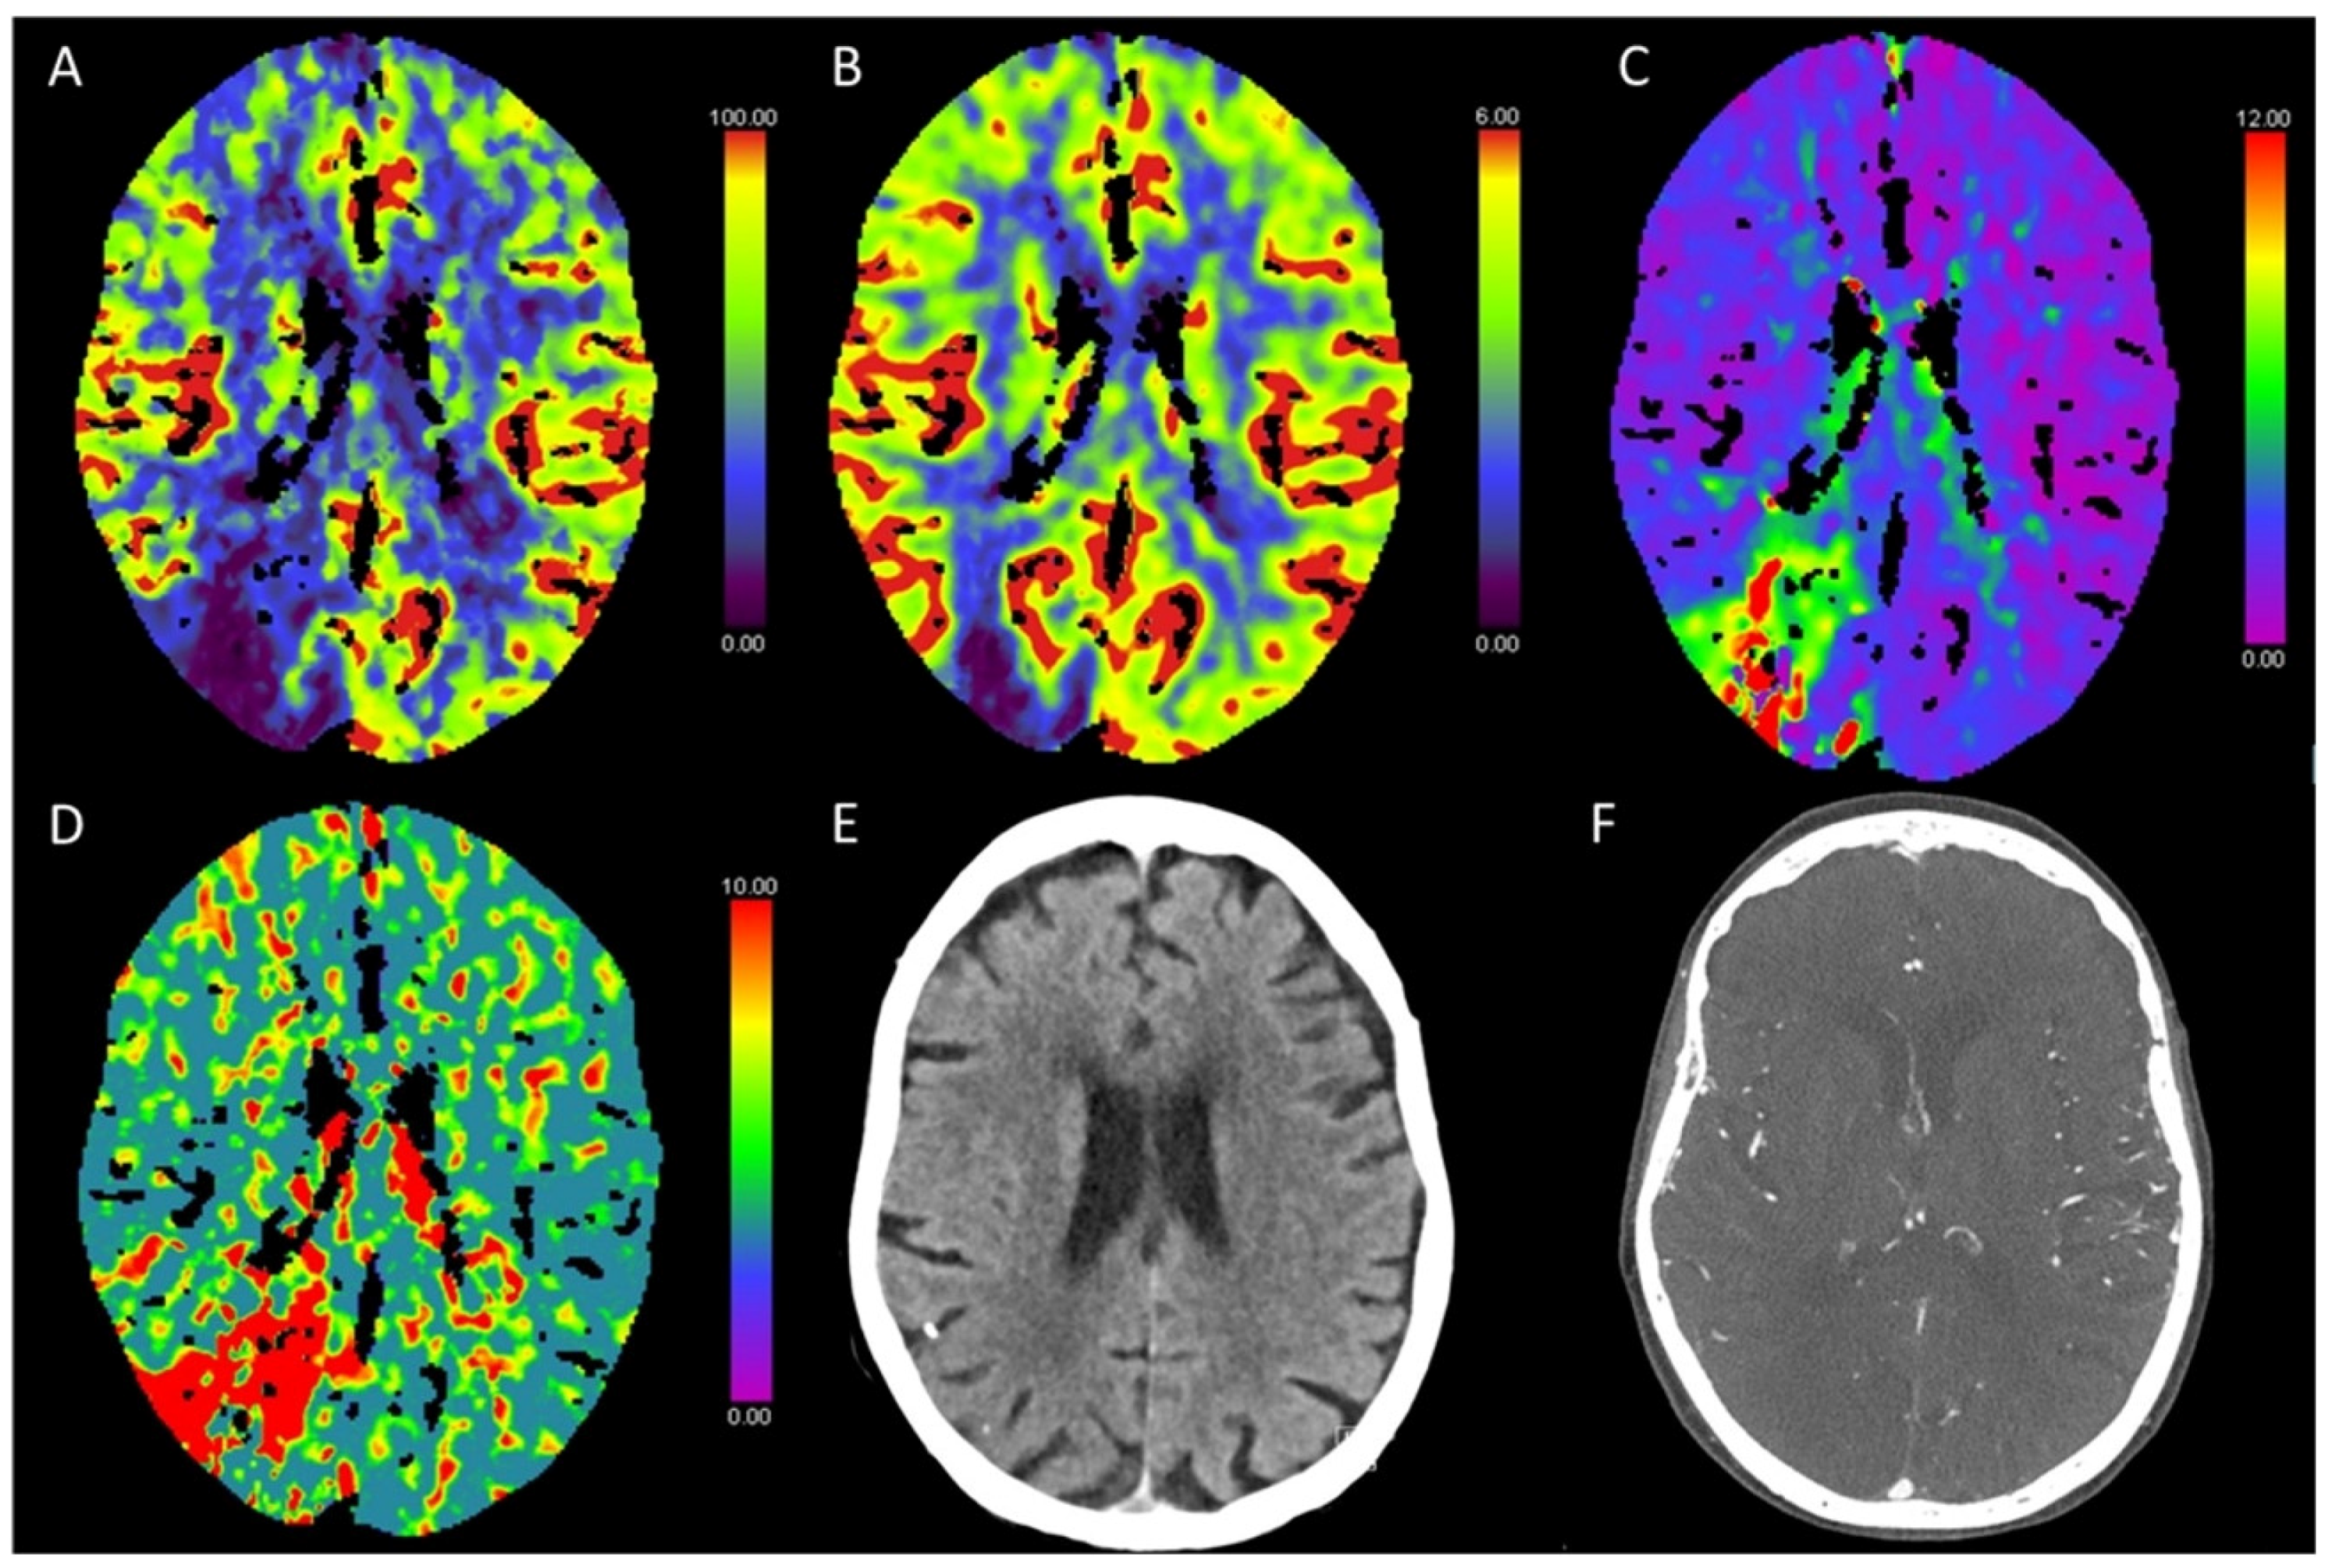

3.3. Global Hypoxic-Ischemic Injury/Brain Death